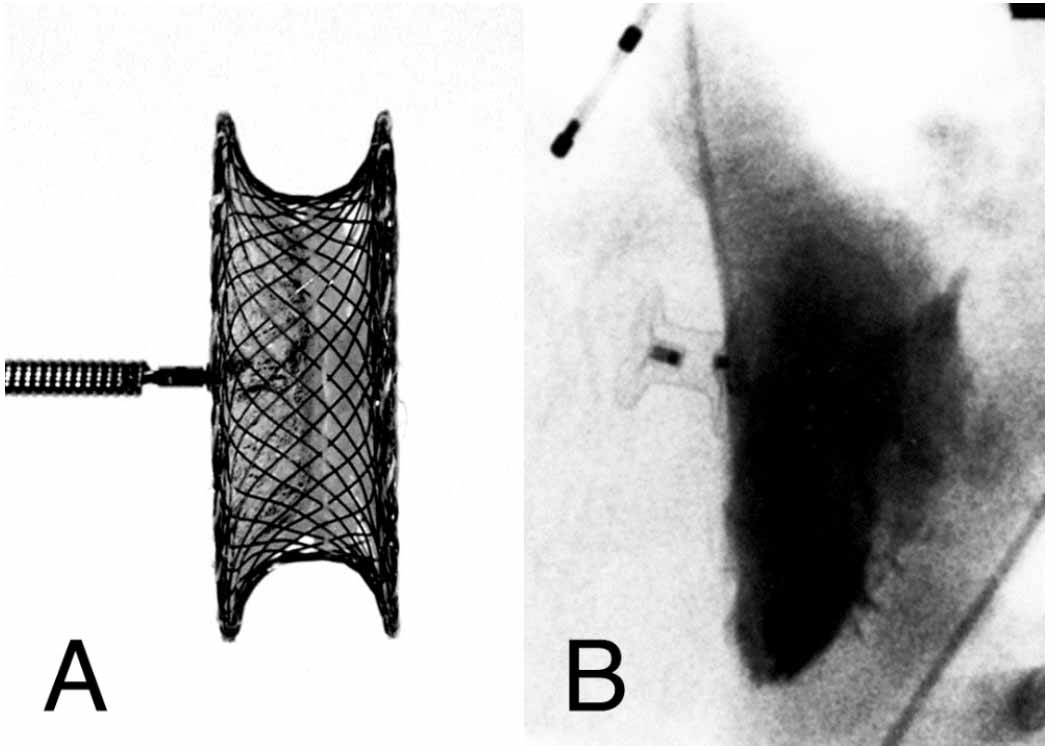

Figure 6

Figure 6 Legend: In A, a muscVSO device has been implanted with a "cobra" deformity of the RV disc, probably caught in RV trabeculations in the apex. Within 24 hours, the RV disc had reformed within the beating heart. Comparing the device in A with images from a heart catheterization 2 months later (B), it is clear that the waist does not completely expand when the RV disc is constrained, and residual shunts are more likely.